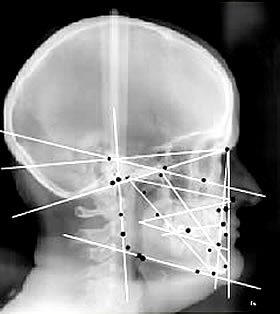

Je suis technicien en prothèse dentaire, spécialisé en occlusion dentaire par analyse céphalométrique

analyse céphalométrique pour déterminer la bonne posture

1992, je découvere l'analyse céphalométrique

A ce moment, je comprends l'importance de l'équilibre du trio crânien (mandibule, crâne et cervicales). Ce trio fonctionne obligatoirement avec le trio bassin.